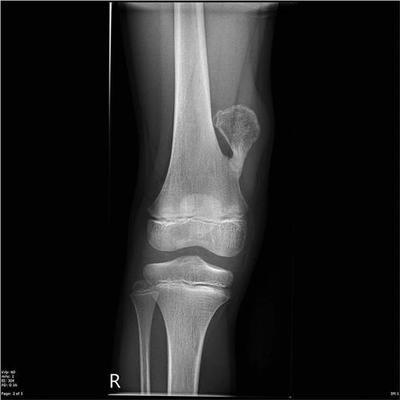

X线片可见近干骺端部位的骨性突起,基底部有时较宽,有时较窄,蒂部与骨干相连,髓腔彼此相通。突起的表面为软骨帽,不显影,所以肿瘤的实际大小可能要比x线平片上要大。和x线相比,CT和核磁共振对位于骨盆、肩胛骨和脊柱上的骨软骨瘤能够更清楚的显示软骨帽的范围及与周围软组织的关系,具有更好的显示效果。